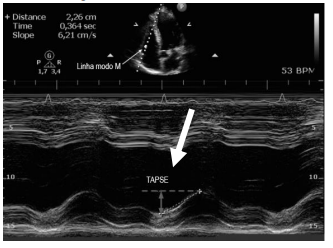

Observe a imagem abaixo:

A seta na imagem indica TAPSE que consiste:

Os valores de TAPSE de =1.9cm (nl>1,6cm) onda S 13(nl>

10), indicam: